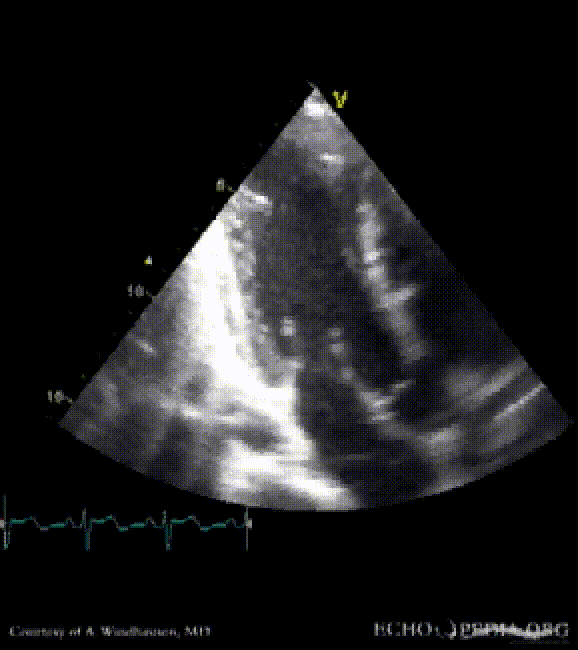

Severe Hypertrophic Cardiomyopathy (HCM)

Case description: Severe Hypertrophic Cardiomyopathy (HCM)

Courtesy of: A. Windhausen, AMC, The Netherlands

A2CH view A4CH view